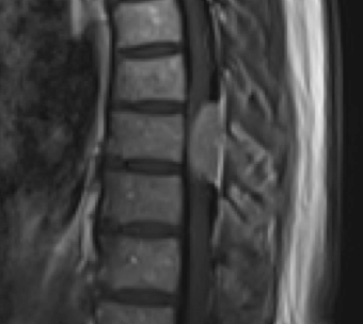

Preoperative MRI T1w demonstrating a large enhancing tumor with severe cord compression

This is a 55-year-old female with no past medical history who presented electively with a 10 month history of progressively worsening mid back pain radiating across the chest, and gait disturbance. Pain was especially worse at night and when laying flat. Her exam was pertinent for severe ataxia when ambulating, and elevated deep tendon reflexes in the lower extremities. She had severe and debilitating symptoms, as demonstrated by her Visual Analog Scale (VAS) and Oswestry Disability Index (ODI) of 9/10 and 64/100, respectively. MRI of the thoracic spine with and without contrast demonstrated a large intradural extramedullary homogenously enhancing mass at T8, resulting in near obliteration of the spinal canal and severe cord compression. She was referred to Dr. Xavier Gaudin for neurosurgical management.